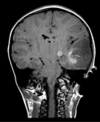

Q

35 anos, Masculino

A

Craniofaringioma adamantinomatoso

Craniofaringioma adamantinomatoso Crianças Lesão suprasselar com componente sólido e cístico; lobulado; calcificação anelar ou nodular presente em quase TODOS os craniofaringeomas pediátricos; Componente cístico proeminente e componente sólido pequeno, mas com realce.